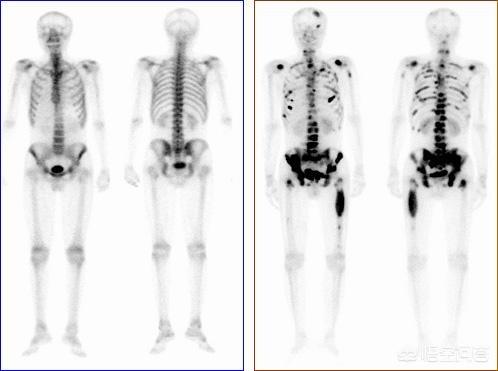

がんの既往歴がなく、家計に余裕がある患者には、全身にがんの疑わしい病変がないかスクリーニングするためにPET-CT検査を行うことが推奨され、これにより腫瘍病変の有無、進行度、どのような転移病巣があるかなどを適切に判断することができる。

がんの既往があり、その時点で悪性度が高いと判断されれば、全身骨シンチで骨転移の有無を調べることができる。同時に、転移部位の骨破壊の程度を磁気共鳴検査で明らかにすることができる。

疼痛は骨転移のほとんど(80%以上)の初期症状であり、一部の転移は非常に若年で発現する。骨痛、骨折、アルカリホスファターゼ上昇、高カルシウム血症などの骨転移が疑われる乳癌に対しては、骨放射性核種スキャン(ECT)を行うことができる。PET/CTはECTと同程度の感度で特異度が高く、乳がん骨転移の治療後の経過観察に使えるという研究もあります。診断が困難な場合は、必要に応じて骨の一部を切除して病理検査を行うこともある。

溶骨性、造骨性、混合性骨破壊のX線所見も、転移性骨癌の可能性を考慮すべきである。転移性骨腫瘍を検出するには、適時の骨スキャンが感度の高い方法である。